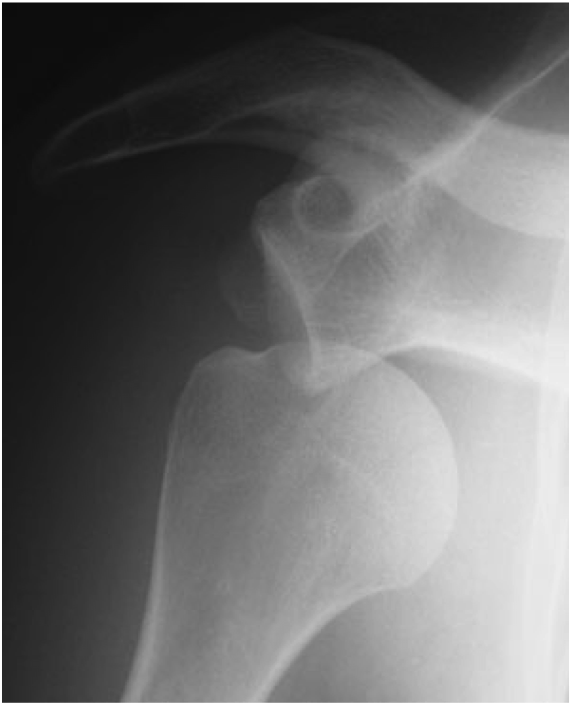

Lorsque vous souffrez d'une affection qui touche vos articulations et/ou vos ligaments, le meilleur choix est de vous adresser à un médecin ou un chirurgien de la clinique du sport Paris. Même si vous n'êtes pas sportif, nos compétences sont faites pour vous. Les principaux traumatismes se situent aux articulations du genou, de l'épaule, de la hanche ou de la cheville, mais nous pourrons traiter vos pathologies osseuses, tendineuses et ligamentaires quelles qu'en soient l'origine. Nous disposons de plateaux techniques modernes, et d'un service d'imagerie médicale permettant les examens nécessaires tels qu'une radiographie, échographie, scanner, IRM, EOS etc. Notre cabinet de chirurgiens du sport vous accueillera si votre cas requiert une opération, comme l'opération de la coiffe des rotateurs et vous conseillera sur la meilleure marche à suivre avant de traiter votre traumatisme par voie chirurgicale. Vous pouvez prendre rendez-vous directement sur notre site.

Inutile d'être sportif pour s'adresser à notre clinique. Tout le monde peut avoir, un jour ou l'autre, un souci médical qui concerne une traumatologie des membres et articulation. Que ce soit une maladie dégénérative ou suite à une blessure due à une pratique sportive, un spécialiste de notre clinique vous prodiguera les soins adaptés à votre physiologie. Le personnel qui travaille chez nous est amené à traiter des traumatismes du genou, de la hanche, de la cheville, de l'épaule. Vous aurez affaire à des kinésithérapeutes pour des séances de rééducation, à des médecins du sport, mais également à des chirurgiens du sport selon votre pathologie. Les lésions du ligament croisé du genou ou bien les ménisque fissuré sont parmi les motifs de consultations les plus fréquents, avec plus de 1000 ligamentoplasties effectuées tous les ans par les chirurgiens de notre équipe. Tous nos praticiens sont experts dans leur domaine d'intervention. Concernant toutes vos pathologies sportives ligamentaires, qu'il s'agisse d'une luxation d'épaule ou d'une entorse, que votre état nécessite une intervention chirurgicale ou non, votre prise en charge multidisciplinaire (kinesithérapeute, podologue, médecin du sport et chirurgien du sport) sera de qualité égale et constante. Si ous avez besoin d’une prothèse articulaire (prothèse de genou, de hanche ou d’épaule), nos spécialistes seront là pour vous faire bénéficier des dernières technologies (planification de la prothèse avec scanner 3D, guides de coupe sur mesure et prothèses sur mesure), vous pourrez reprendre vos activités après quelques semaines de rééducation.